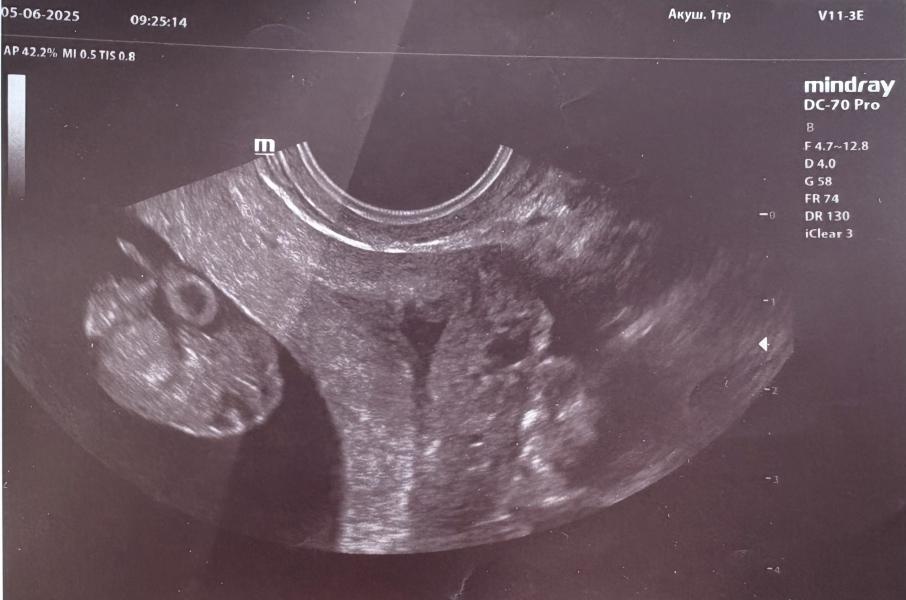

УЗИ на раннем сроке: бьющееся сердечко и долгожданный сюрприз для будущих родителей! Детали

😍 сегодня ходила на узи. Хочу родителям сюрприз сделать, по этому пошла. Показали как бьется сердечко, он еще такой маленький, но такой любимый 😍